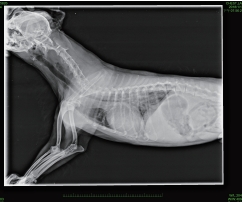

影像科

心臟胸腔科